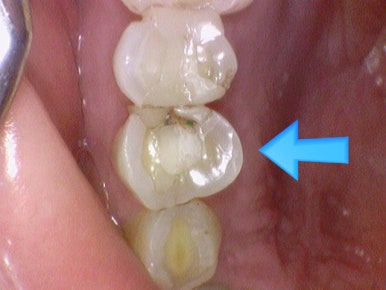

깨진 치아를 지르코니아 크라운으로 치료

위 케이스 지르코니아 크라운을 옆에서 본 사진 ↓